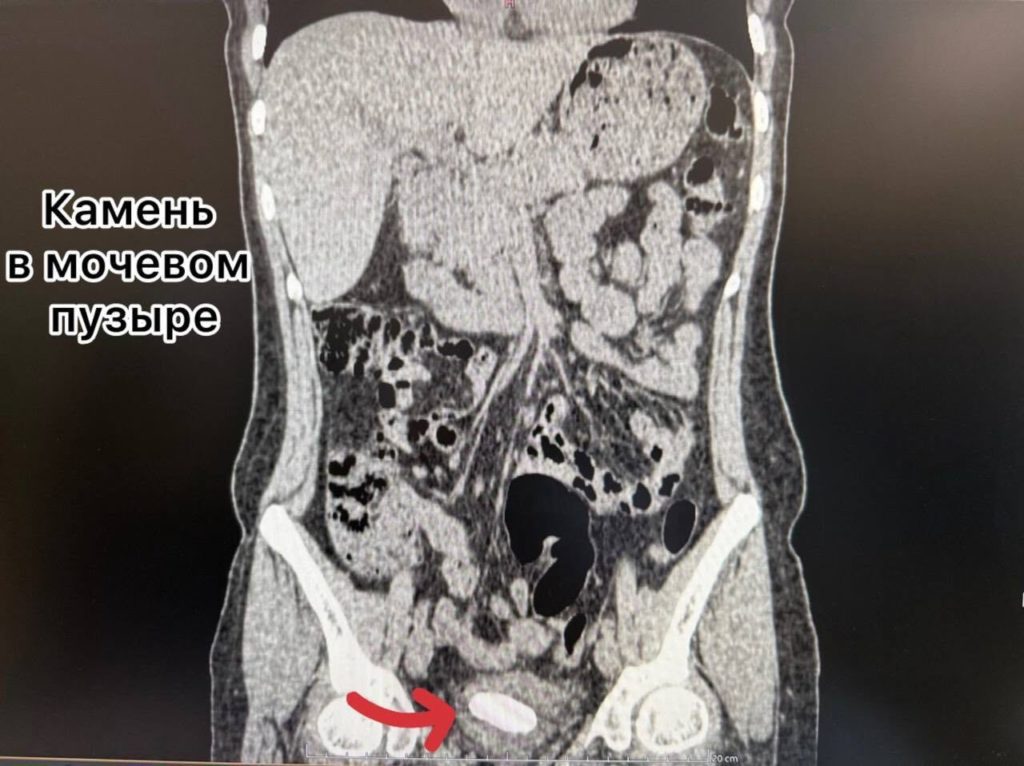

За это время на трубке образовались солевые отложения, сформировавшие крупные камни как в почке, так и в мочевом пузыре.

Помощь была оказана в приоритетном порядке по системе «зелёного коридора», так как пациентка является супругой участника СВО. Перед врачами стояла сложная трёхэтапная задача: удалить камень из почки, раздробить и извлечь камень из мочевого пузыря и убрать сам инкрустированный стент.

Урологи Александр Певчев и Мадина Абдуллаева провели уникальное сочетанное вмешательство за одну операцию. Через минимальный прокол в пояснице ультразвуком был разрушен почечный камень, а через естественные пути лазером раздроблены и удалены камень из мочевого пузыря и стент. Вся процедура выполнялась с эндоскопическим и рентгенологическим контролем.